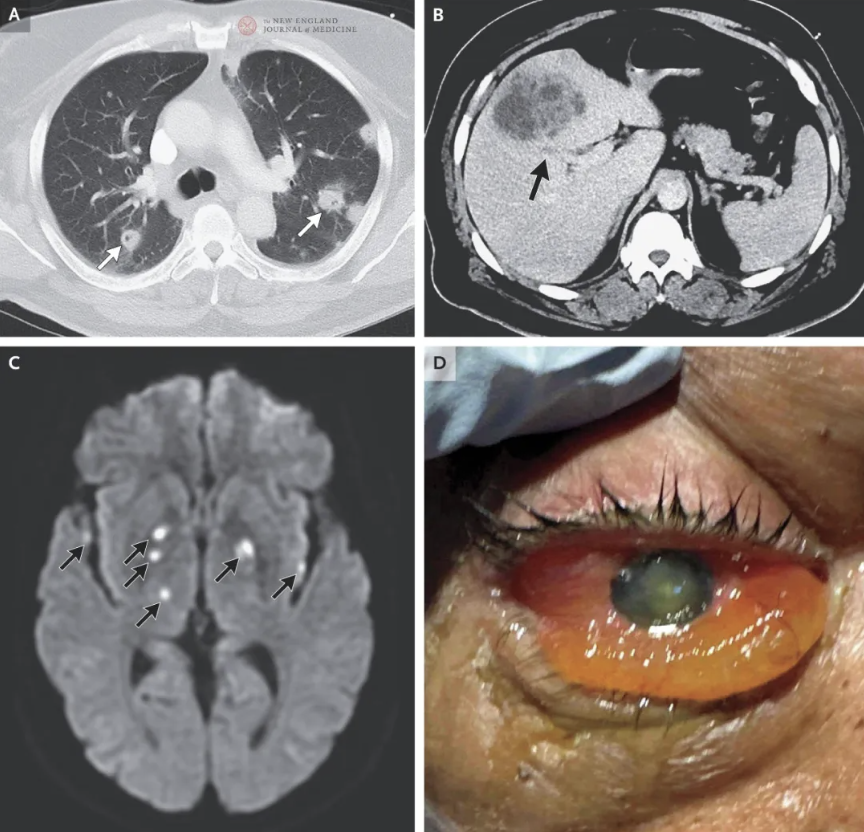

由于角膜混浊严重,合并广泛多层脓肿及巩膜壁缺损,无法安全实施玻璃体切除术。术后患者自述右眼“无光感”,很可能系转院时视力已接近完全丧失,加之术后眼压持续升高所致。尽管尝试多种降眼压措施,右眼视功能始终未恢复。为缓解炎症及眼压升高,开始局部应用糖皮质激素和降眼压滴眼液。入院第一周内,右眼眼球突出和结膜水肿进一步加重(图3A),视力持续为“无光感”。

图3. MGH的临床及头颅MRI影像

住院第8日复查头部MRI示:双侧大脑半球及后颅窝多发病灶出现新发环形强化,弥散受限表现持续存在(图3B)。右眼显示严重睑前软组织炎症,伴显著眼球突出及眼球异常延长。MRI还发现右眼巩膜环形强化,后眶隔区域存在广泛软组织炎症改变,累及右侧眼外肌及泪腺;眼球内侧可见一小型周边强化病灶,考虑为巩膜周围脓肿。此外,MRI显示右侧视神经严重牵拉,沿视神经路径可见广泛神经周围强化(图3C)。

鉴于患者右眼视力无恢复可能,且存在眼球自发穿孔风险,加之接受规范抗感染治疗后仍出现进行性眼眶感染恶化,医生最终决定行右眼球摘除术以控制病情。